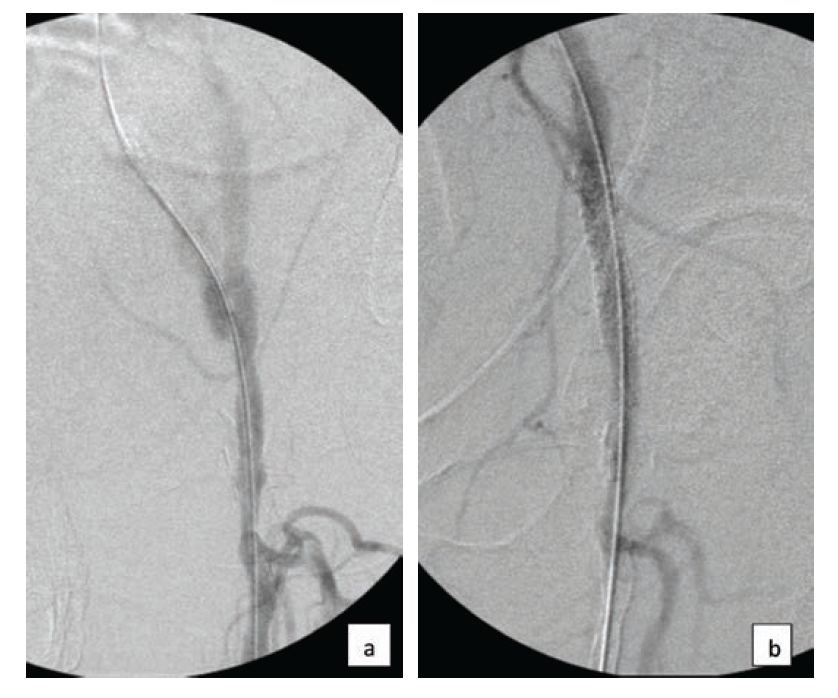

Like many operators these days, we use ultrasound-guided access in almost every case. Starting with a micropuncture needle and sheath is safest, if not necessary, in all cases. Our first angiogram is usually of the access site in order to determine that we are in the optimal location and, in the case of femoral artery access, whether a closure device may be used at the end of the case. We use closure devices in 97% of our femoral artery access cases,5 which results in faster time to ambulation. Additionally, some patients travel great distances to home after the procedure,6 and using a closure device helps to prevent a late bleed at an inopportune time. I predominantly use a suture-based device, but also have collagen-plug type devices when the former is not applicable, as in heavily calcified access vessels. It is important to be familiar with the complications that can occur if a closure device is not properly deployed, or if the device malfunctions, and know how to resolve the situation. Becoming well acquainted with a couple of closure devices rather than many devices may help to build operator skills and minimize the risk of unsuccessful deployment. In my own experience, I have rarely caused acute access site closure from improper closure device deployment, which usually occurs when a closure device is used in a diseased vessel (Figure 1). All operators must know how to respond to this scenario. Follow activated clotting time (ACT) throughout the case, usually after the initial heparin bolus, and at least every 30 minutes thereafter, to minimize the risk of thrombus generation, particularly when there is diminished flow and in tibial interventions. The variability in the response to standard weight-based administration can be striking between individuals. The presence of thrombus will usually require additional heparin as well. Only the ACT will determine the proper dosing of heparin during the case. The range should be 200 – 300 seconds, depending upon circumstances.